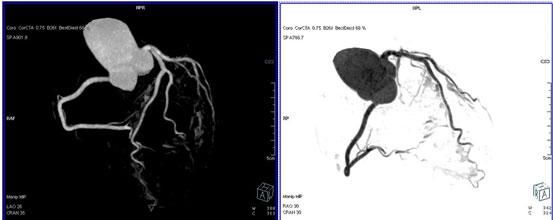

3.對于斑塊性質的确定,CT優于DSA:

二、多層螺旋CT頭頸部及體部血管成像技術:

該機掃描覆蓋範圍廣、時間短,多種後處理分析軟件能顯示各血管細小分支,可以清晰顯示動脈瘤、動脈夾層、血管畸形、血管狹窄及動脈粥樣硬化斑塊等,适用于頭頸部血管成像、肺動脈成像、胸腹部血管成像及四肢血管成像。

1.顱腦血管成像:

動脈瘤

2、頸部血管成像